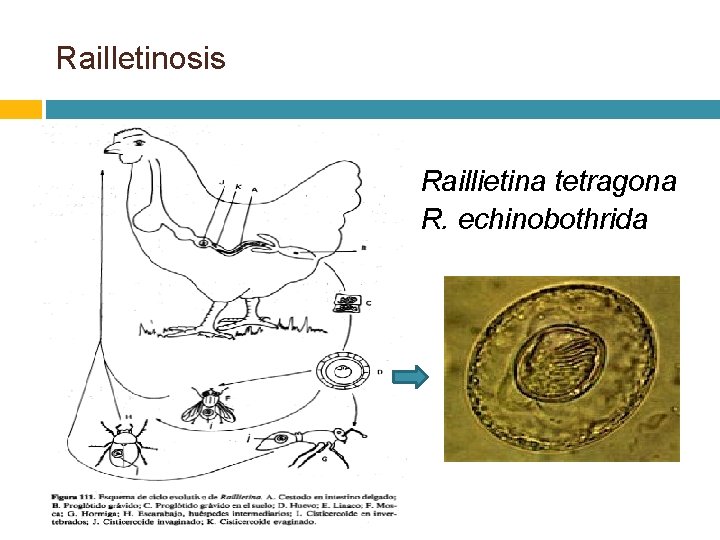

Railletinosis Raillietina tetragona R. echinobothrida